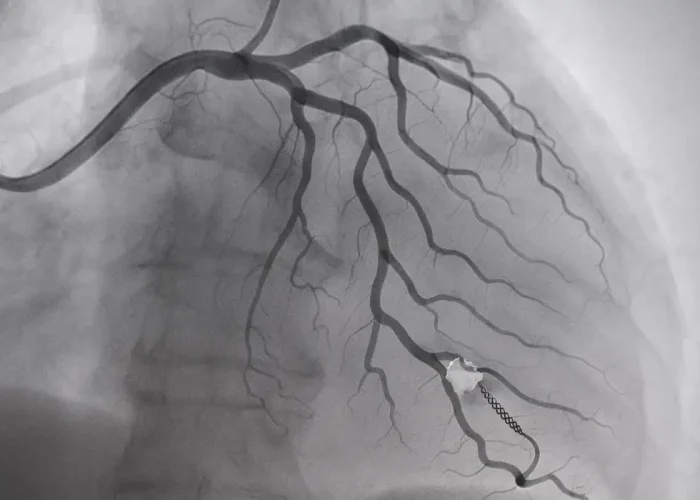

رأب الوعاء هو إجراء غير جراحي يتم باستخدام قسطرة بالونية صغيرة تُدخل إلى الشريان المسدود. يتم نفخ البالون لإزالة الانسداد أو التضييق في الشريان، مما يتيح استعادة تدفق الدم. في بعض الحالات، يتم وضع دعامة (Stent) لتثبيت الشريان ومنع إعادة الانسداد.

- في كثير من الحالات، يتم إدخال دعامة معدنية لضمان بقاء الشريان مفتوحًا.

أنواع الدعامات المستخدمة في رأب الوعاء

- الدعامات المعدنية العادية (Bare Metal Stents):

تُستخدم لتوسيع الشرايين ولكنها قد تزيد من خطر إعادة الانسداد. - الدعامات الدوائية (Drug-Eluting Stents):

تحتوي على أدوية تُفرز تدريجيًا لتقليل خطر إعادة الانسداد. - الدعامات القابلة للامتصاص الحيوي (Bioabsorbable Stents):

تُصمم لتتحلل بمرور الوقت، مما يُقلل من المضاعفات طويلة الأمد.